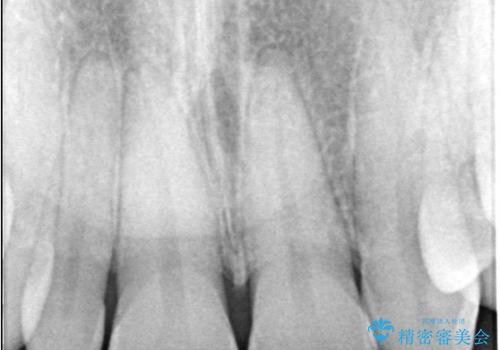

- 「前歯の見た目が気になる」を主訴に来院された患者様です。

右上2が矮小歯だったので、オールセラミッククラウンで審美修復しました。